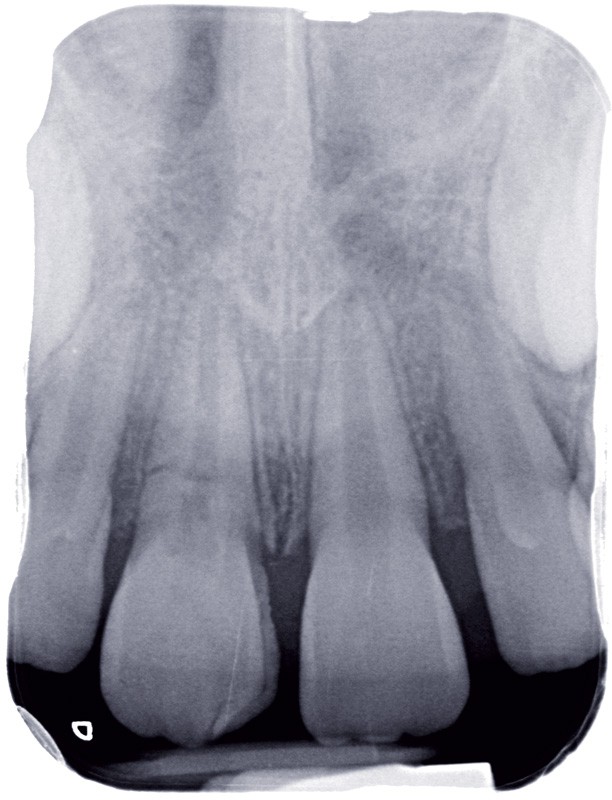

a à d Jeune patiente âgée de 8 ans, adressée suite à un traumatisme survenu 3 semaines auparavant, pour l’extraction de sa 21. La vue clinique montre un saignement ligamentaire, une mobilité coronaire et une fracture coronaire amélodentinaire longitudinale partant de l’angle mésial et se poursuivant en direction radiculaire sous-gingivale (a). Un test de vitalité positif indique que la dent est vitale, la radiographie permet de poser le diagnostic de fracture coronoradiculaire, et d’objectiver l’immaturité radiculaire (stade 8 de Nolla) (b). Une contention est mise en place et la plaie dentinaire coronaire est scellée au mieux par collage afin de limiter le risque d’une complication infectieuse (c). A 15 jours la dent est vivante et aucune complication n’est apparue (d). La patiente est revue après 3 mois pour déposer la contention, le test de vitalité est positif, et la radiographie de contrôle montre une apexogenèse en cours (e). Cependant la gencive s’est invaginée dans le trait de fracture (f). La zone est débridée sous microscope (g) puis scellée et reconstituée à l’aide d’un adhésif SAM et d’un composite fluide (h). Le contrôle radiographique à 6 mois est satisfaisant (i). Ce cas clinique illustre le fort potentiel des pulpes jeunes et du ligament alvéolodentaire à résister aux agressions et à assurer les fonctions dentinogénétiques et l’édification radiculaire.